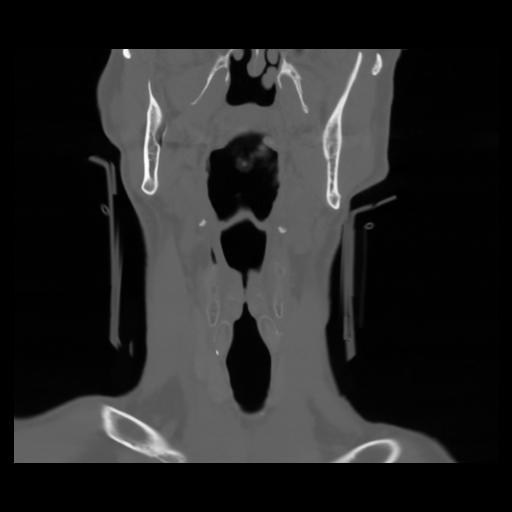

13 P.BLANDAS,,Coronal,2.000,P.BLANDAS,Coronal,